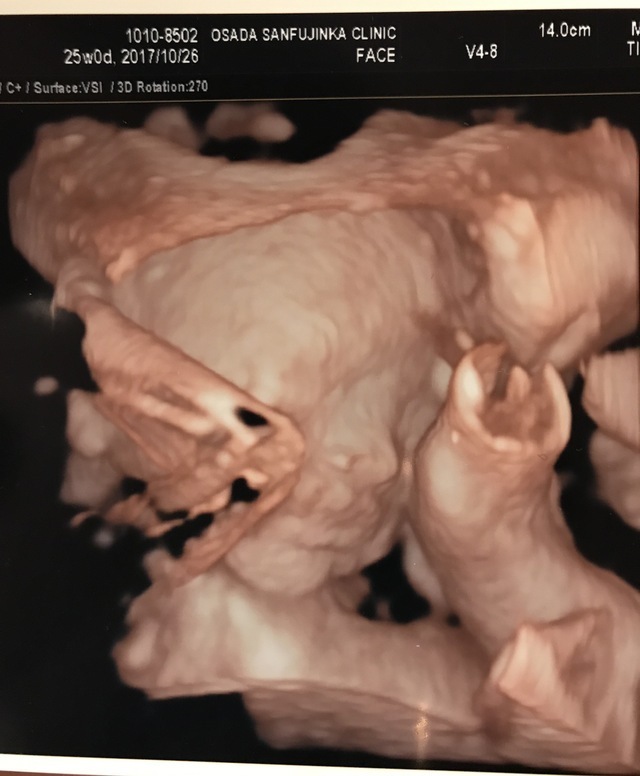

25週0日(25w0d・男の子)|まぁりん さん(31歳)

エコー写真撮影時のエピソード:

初めて顔の様子がハッキリわかった4Dエコーです!それまでなかなか4Dエコーをしてもらえず、ずっと顔が見たいと思っていました。里帰り先の産婦人科で撮っていただいたものです。旦那もこのエコー写真を見てとても喜んでいました。

私は4回の流産を経てやっとここまできたので、エコー写真をもらうたびにうれしくてたまりません!これからも大切に育てていきます。大きくなぁれ!